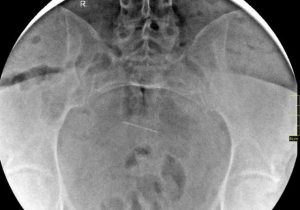

Aceasta mai povesteşte că în anul 2013 a căzut „amorţită, paralizată pe moment“, fiind dusă la Spitalul „Sf. Spiridon“, unde în urma unei radiografii s-a constatat că există un „corp străin ascuţit şi subţire“, vizibil foarte clar, confirmat şi de medicii de la alte două spitale unde a ajuns în acea seară, indicând că este „un ac medical care a migrat între oasele bazinului“. Femeia mai spune că aceasta a fost singura operaţie suferită în cursul vieţii şi că a mai fost consultată de alţi doi chirurgi care susţin că este vorba despre un ac chirurgical în abdomen. „Acum fac multe legături: de ce nu pot ridica, de exemplu la cumpărături sacoşa mai grea, de ce mă doare în zona lombară, de ce obosesc foarte repede şi mă aşez cu greu jos, de ce îmi amorţeşte destul de des mijlocul şi toată zona lombară şi pelviană. Oboseala ar putea fi de la Hepatita B sau diabetul de care sufăr, dar amorţelile, durerile lombară şi pelviană de unde? Şi toate aceste dureri de ani buni“, povesteşte femeia.